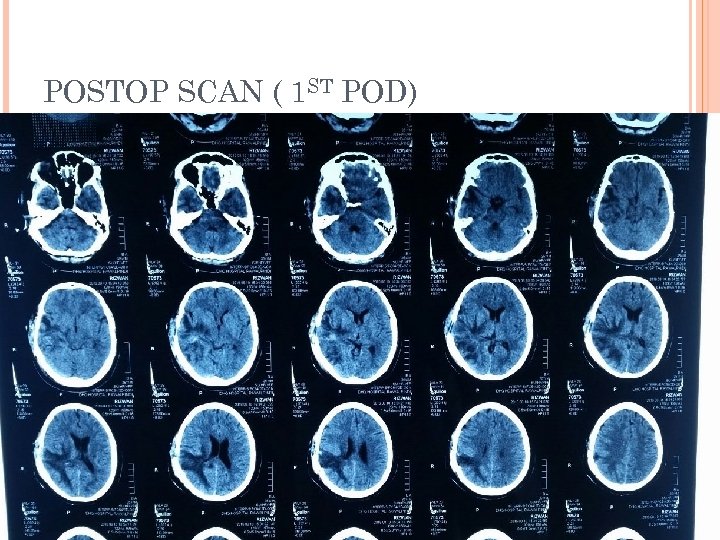

CHECK CT SCAN ( 1 ST POD)

POSTOPERATIVE PERIOD Patient conscious oriented Taking orally Pus for C/S showed proteus mirabilis. Discharged on 4 th POD with iv antibiotics ( 4 weeks ). Advised: Wound care Daily dressing OPD follow up after 10 days.

POSTOP SCAN ( 1 ST POD)